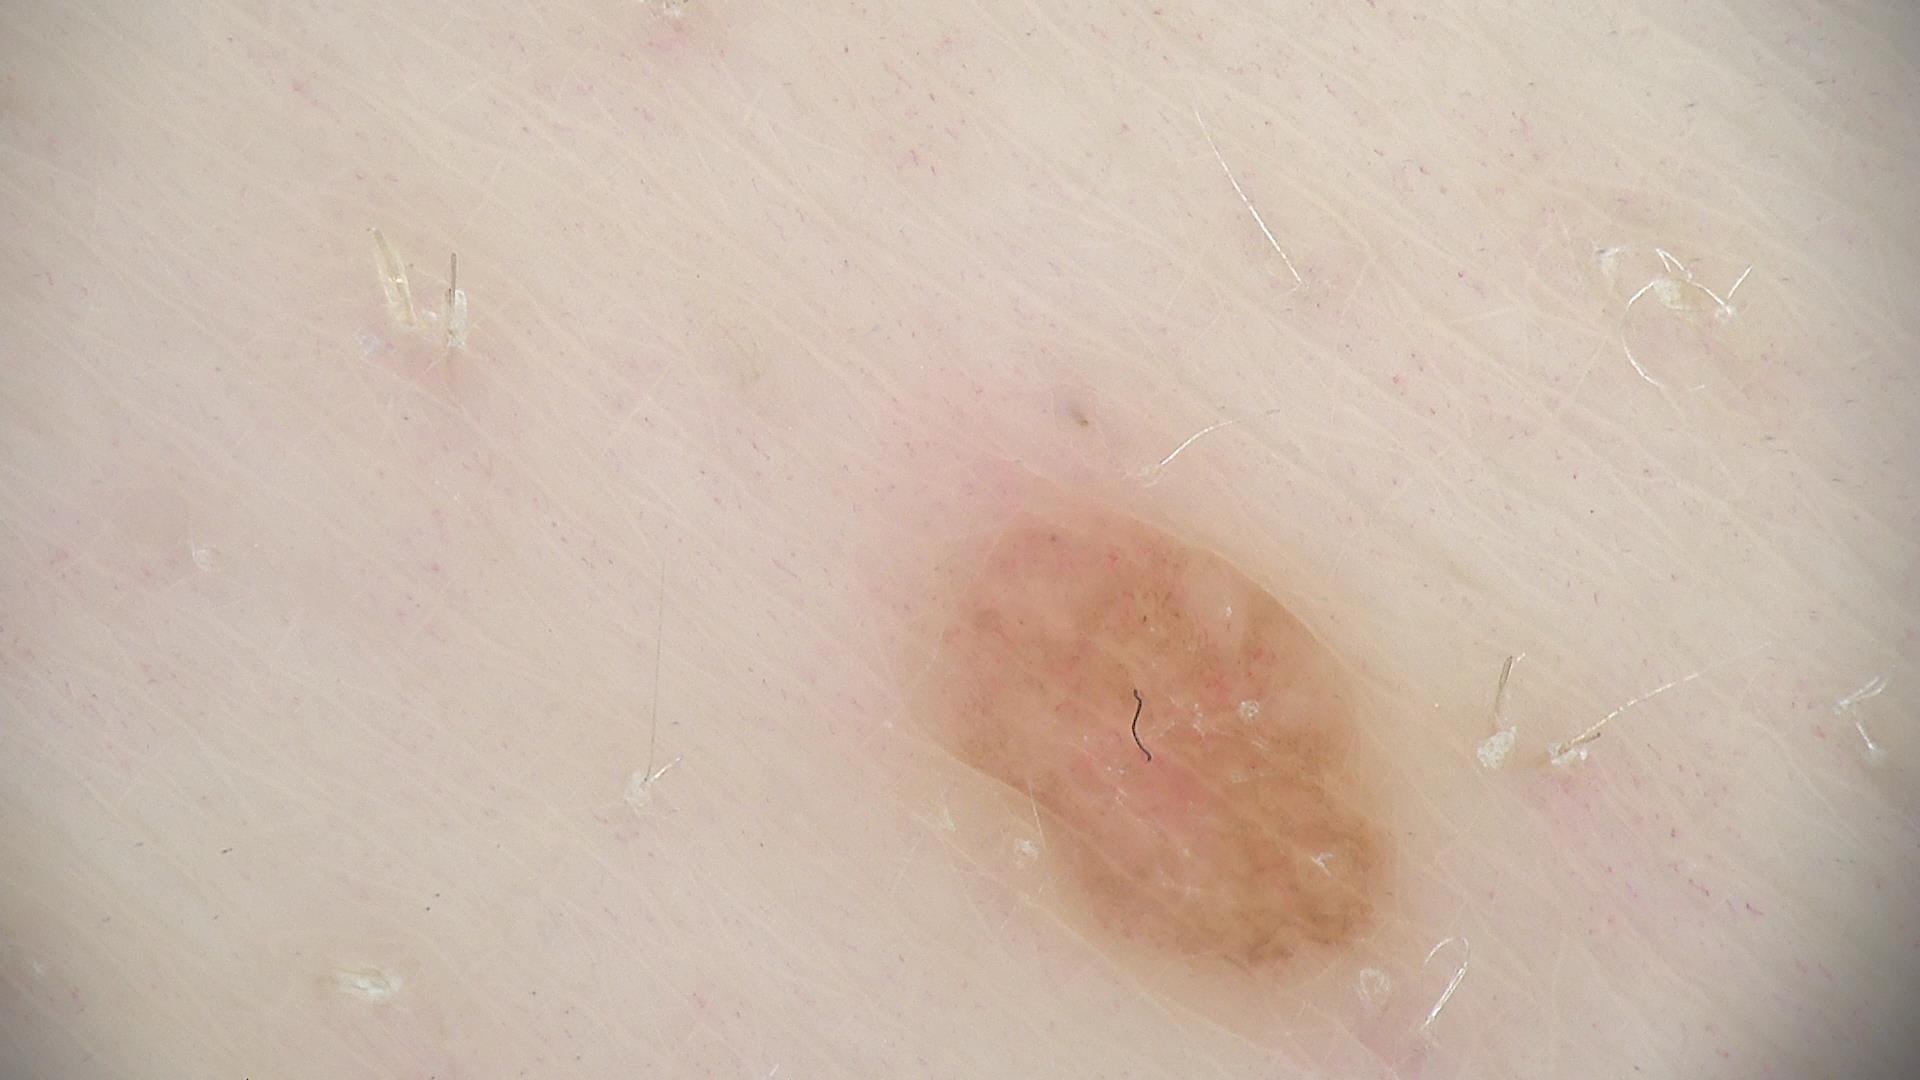

ISIC_7874084

diagnosis_1

Benign

diagnosis_2

Benign melanocytic proliferations

diagnosis_3

Nevus

diagnosis_4

Nevus, NOS, Dermal

image_type

dermoscopic

melanocytic

True